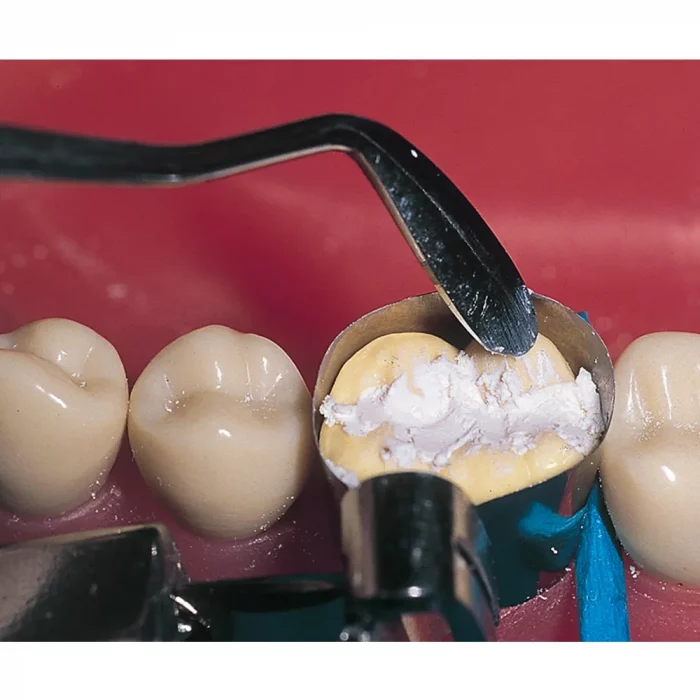

- Easy application with suitable instruments

Description-Ammdent Cavitemp Temporary Filling Cement is a dependable solution for temporary cavity restorations, designed to self-cure in humid conditions. Composed of Zinc oxide, Calcium Sulphate, Zinc Sulphate, and select excipients, it provides effective sealing and drug impermeability. The application process is simple, involving the filling of a wet cavity with an instrument, with hardening beginning within minutes. For best results, it’s recommended to avoid chewing pressure on the treated area for at least two hours. While deep cavities may not require filling, the product is ideal for pressure-free drug closures. Removal is easy using a rotary instrument or stiff probe, making it a convenient option for dental practitioners. Cavitemp offers an efficient and reliable solution for temporary dental restorations in clinical practice.